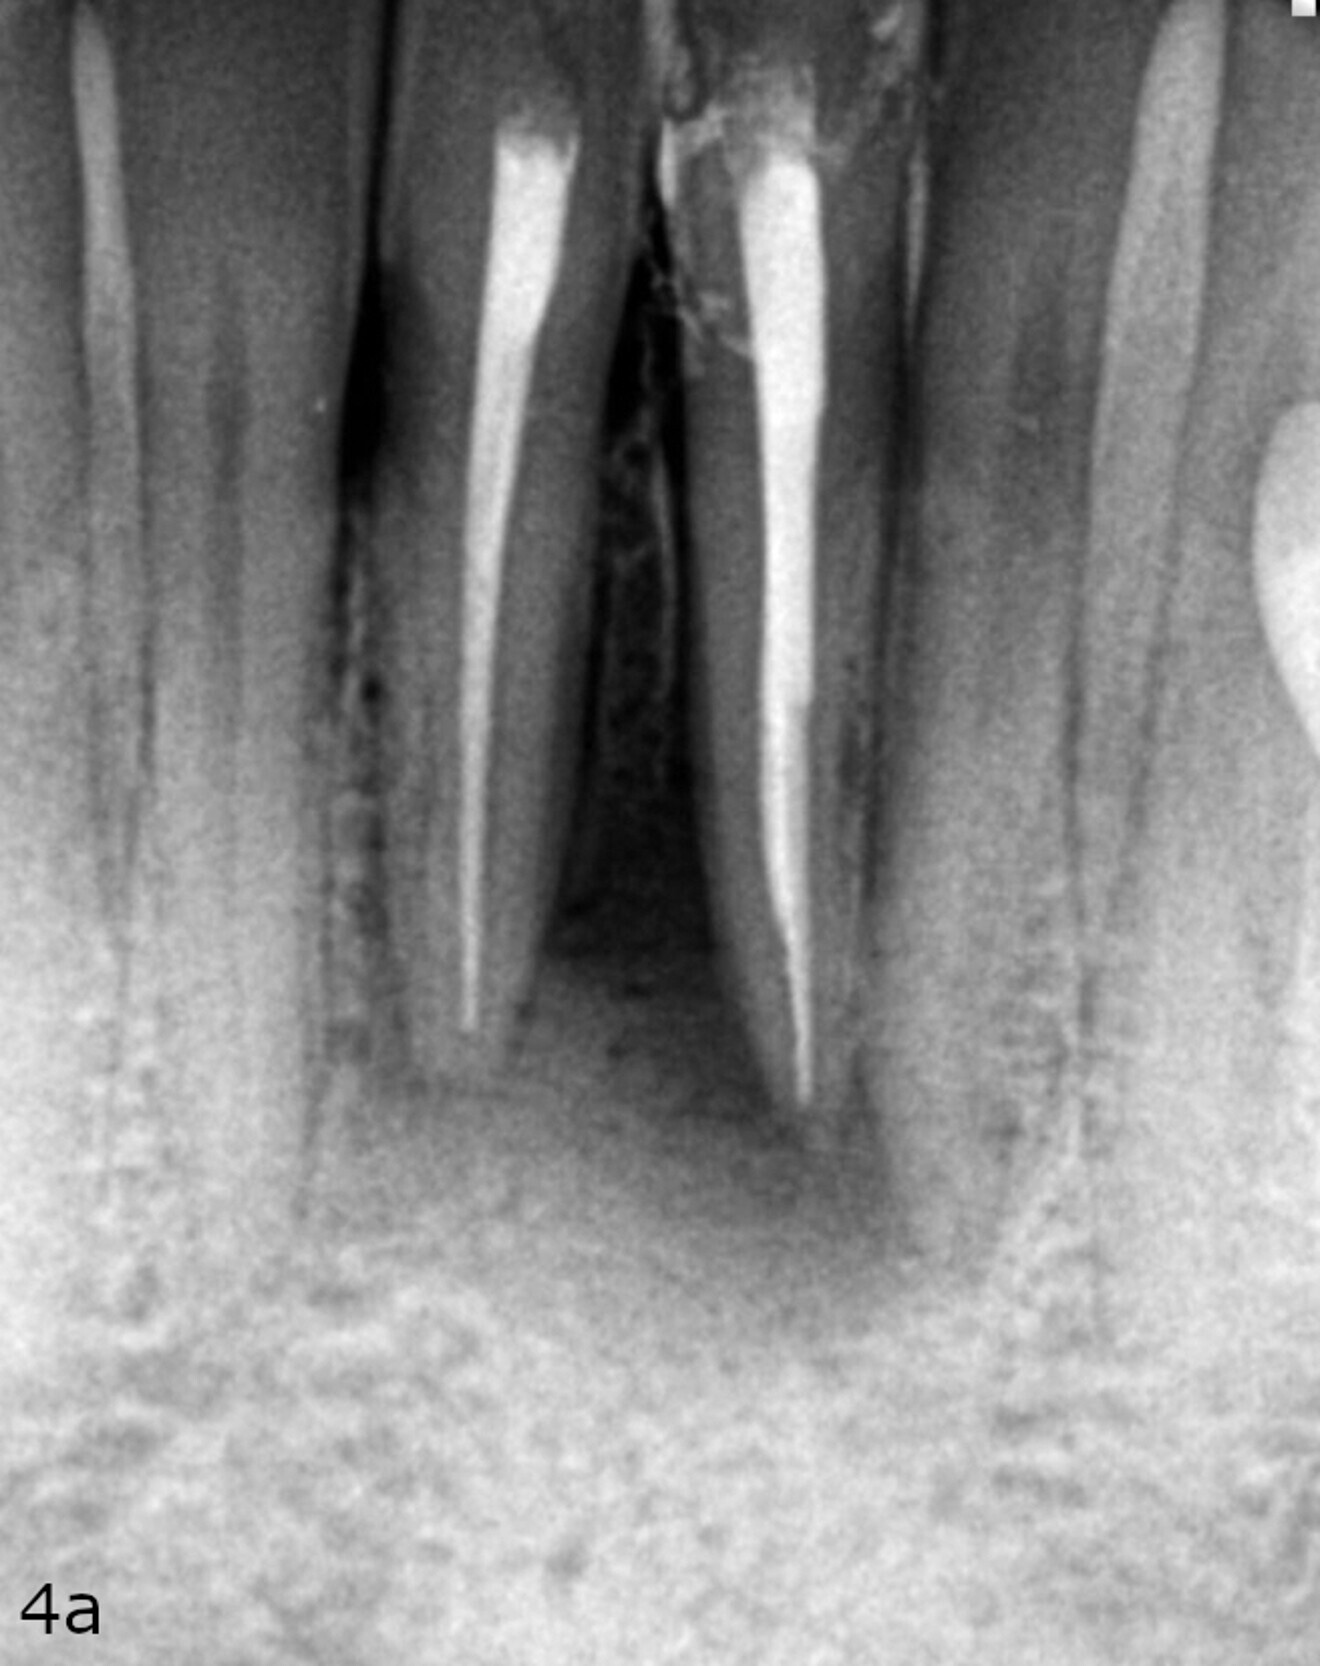

A radiograph was taken of the immediate postoperative situation and at the nine-month follow-up. Comparison showed bone apposition between the two central incisors (Fig. 4). An i-CAT scan was also taken at the nine-month follow-up to check the bone growth. The horizontal view, taken at the same level as that taken preoperatively, clearly showed the reduction of the gap from 14.11 mm to 4.42 mm at the cortical level and the trabecular bone showed the same trend in healing (Fig. 5). The vertical view showed that the bone on the buccal plate was growing towards the root and growing vertically (Fig. 6). Almost 8.2 mm in height had been regained and in direct contact with the roots of the teeth. Indeed, when provided with a scaffold on which to grow, the bone can grow in all directions, including vertically, where there was an open periodontal pocket. This is the major breakthrough of this technique. No bone grafting material or a membrane was placed. The periosteum was in great condition, and for me, it was the best membrane I could wish for.

Fig. 4a: Radiographs showing the immediate post-op situation ...

Fig. 4b: ... and the situation at the nine-month follow-up.